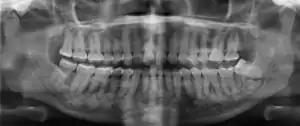

| Florid osseous dysplasia of the mandible | |